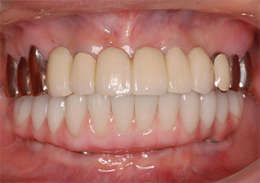

下顎のALL-ON-4①(下の歯のオールオンフォー)

-

- 主訴

- もともと入っているインプラントの周りが腫れ、残りの歯も動いているので力が入らない

- 治療内容

- 下顎右側に以前埋入したインプラントの撤去を行い、歯周病の進行が著しかった残存歯の抜歯を行うと同時にインプラントの埋入を行い、当日仮歯を装着した

- 治療費用

- 下顎ALL-ON-4:4,000,000円(税別)

- 治療期間

- 6ヶ月